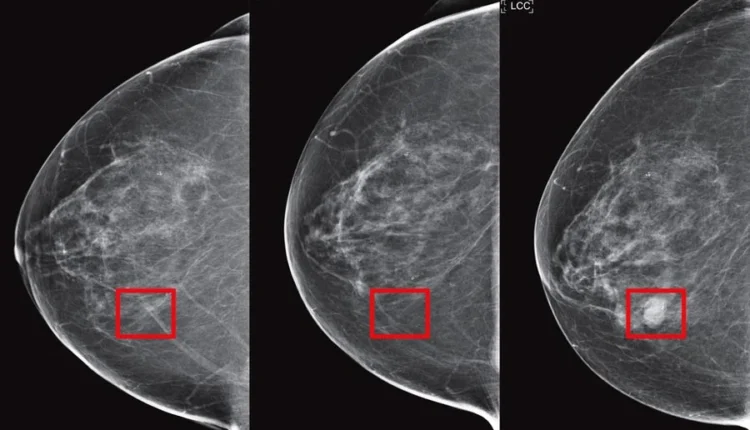

AsymMirai : Une Nouvelle Interprétation

En réponse aux critiques sur l’opacité de Mirai, les chercheurs ont développé AsymMirai, un modèle d’apprentissage profond interprétable. AsymMirai utilise les différences bilatérales locales pour comparer les tissus mammaires gauche et droit, ce qui simplifie l’approche de Mirai tout en maintenant une performance presque équivalente pour prédire le risque de cancer du sein sur une période de un à cinq ans.

Pour l’étude, Jon Donnelly et ses collègues ont comparé AsymMirai à Mirai en utilisant 210 067 mammographies de 81 824 patientes du dataset EMBED (EMory BrEast imaging Dataset) de janvier 2013 à décembre 2020. Leurs résultats montrent qu’AsymMirai offre une précision comparable à Mirai, tout en étant plus compréhensible pour les radiologues. La méthode de dissimilarité bilatérale locale utilisée par AsymMirai met en évidence l’importance clinique de l’asymétrie mammaire comme marqueur d’imagerie pour le risque de cancer.

Donnelly a déclaré : “Nous pouvons, avec une précision étonnamment élevée, prédire si une femme développera un cancer dans les 1 à 5 ans à venir en se basant uniquement sur les différences localisées entre les tissus mammaires gauche et droit.” Cette approche pourrait influencer la fréquence des mammographies, offrant ainsi une surveillance plus ciblée et efficace.

Les résultats ont montré que le modèle simplifié AsymMirai performe presque aussi bien que Mirai pour la prédiction du risque de cancer du sein sur une période de un à cinq ans. En se basant sur les différences entre les tissus mammaires gauche et droit, AsymMirai pourrait devenir un outil précieux pour les radiologues, facilitant des diagnostics plus précis et des prédictions de risque plus fiables. Cela pourrait potentiellement affecter la fréquence des mammographies à l’avenir, rendant les dépistages plus efficaces et mieux adaptés aux besoins individuels des patientes.